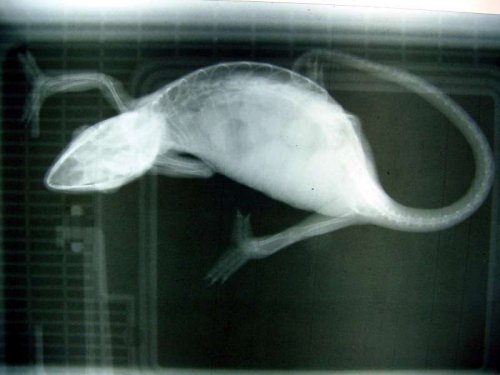

About 4 weeks ago I noticed she was getting even larger than she was and I could feel a hard lump above her hind legs. I took her to the vet and xrays confirmed she was carrying eggs, poorly calcified, unordered, and about full size. I let her go one more week, and another xray. The eggs moved more into lines, and were brighter white. After that xray she was put on calcium glu every other day in hopes to further calcify the eggs and induce contractions. The hard lump I was concerned about never showed in either xray, each time was actually 3 views.

About 4 weeks ago I noticed she was getting even larger than she was and I could feel a hard lump above her hind legs. I took her to the vet and xrays confirmed she was carrying eggs, poorly calcified, unordered, and about full size. I let her go one more week, and another xray. The eggs moved more into lines, and were brighter white. After that xray she was put on calcium glu every other day in hopes to further calcify the eggs and induce contractions. The hard lump I was concerned about never showed in either xray, each time was actually 3 views.